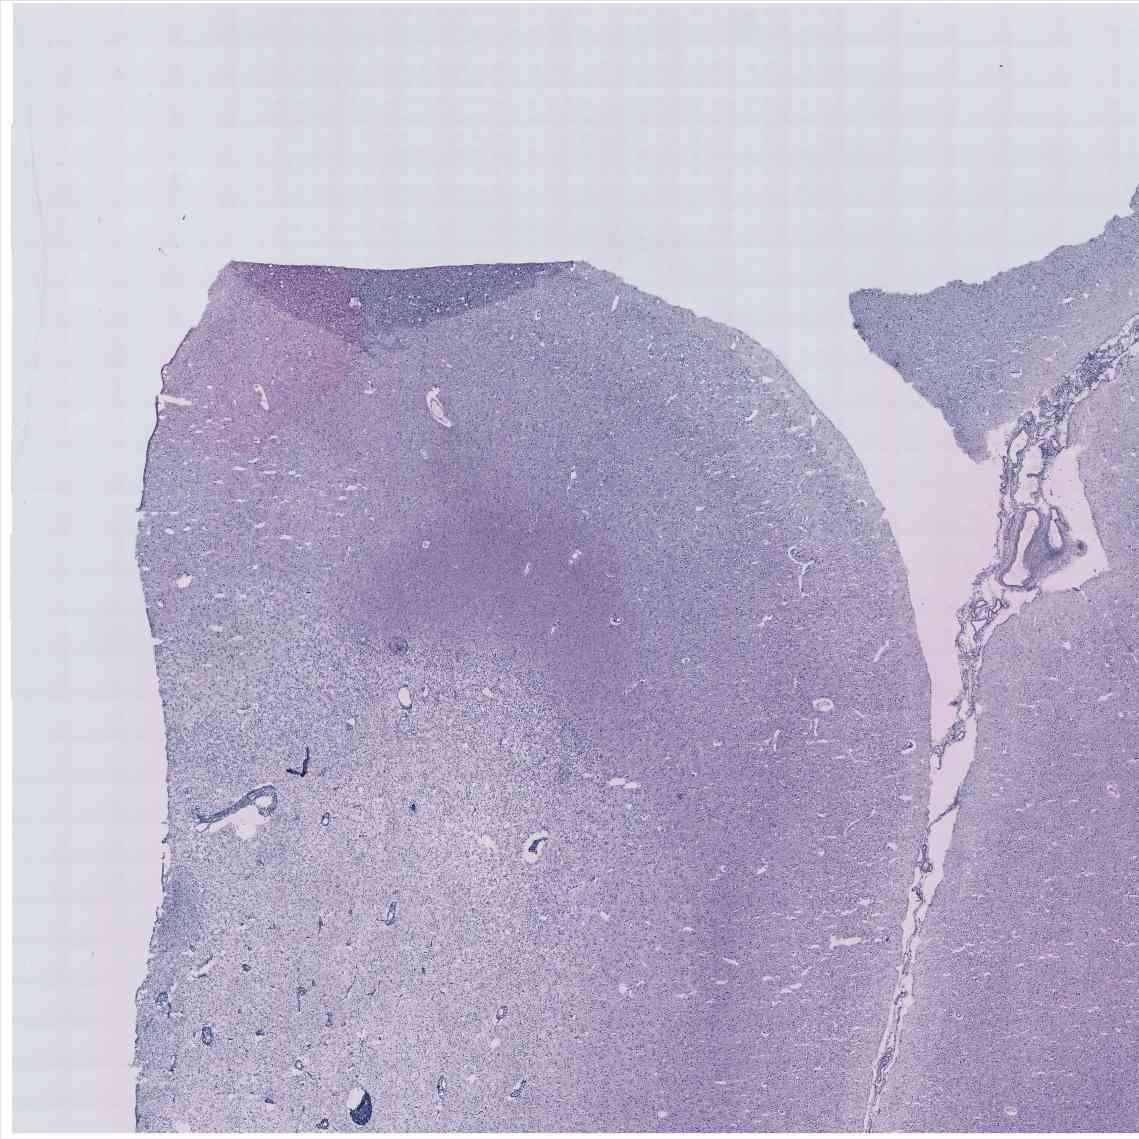

Chip 008 Well C1